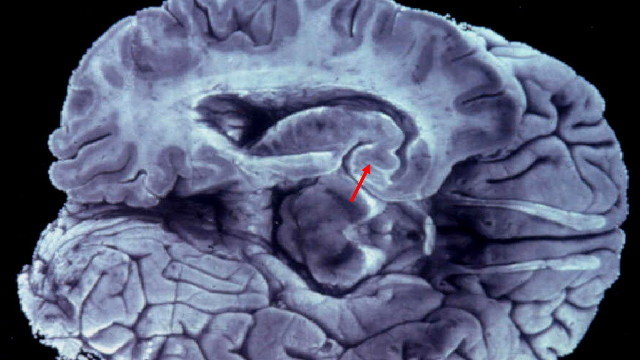

Imagen de un cerebro que muestra lesiones características de la enfermedad de Alzheimer. ARCHIVO